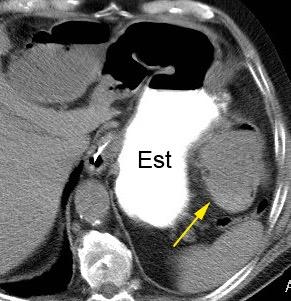

47. INTERPOSICIÓN CÓLICA DE CHILAIDITI

Interposición del colon entre hígado y diafragma

Más frecuente en pacientes con EPOC, cirrosis y ascitis

Incidencia.0,025%-0,28%.

Shinha T. Chilaiditi Syndrome. Intern Med. 2017